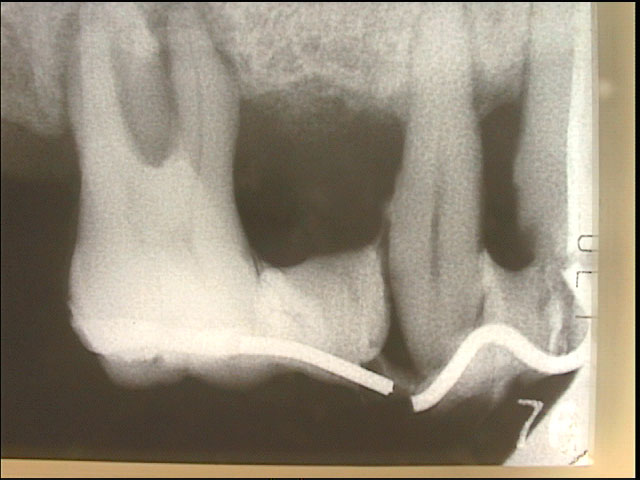

計測データがあれば効果的な咬合圧の負担軽減法を客観的に選択することが可能になります。さらに、選択された治療法の術前、術後の負担軽減効果を評価することもできます。負担軽減法は咬合調整からスプリント(副木)を装着する方法まで色々あります。動揺歯の周囲の歯を含めてスプリント(副木)を装着する方法は最も効果的な負担軽減法です。この治療法は歯の動揺が停止するだけでなく歯周組織の破壊も改善します。7-6(Photo-1~Photo-3)

With measurement data, it becomes possible to objectively select effective occlusion pressure burden reduction method.In addition, it is possible to evaluate the effect of reducing the burden of preoperative and postoperative burden of the selected therapy. There are various ways to reduce burden from occlusal adjustment to a method of installing a splint. The method of attaching the splint including the teeth around the loose tooth is the most effective way of reducing the burden. This treatment not only stops tooth oscillation but also improves periodontal tissue destruction. 7-6(Photo-1~Photo-3)

動揺歯を固定する方法は【仮固定と長期固定装置】があります。動揺歯を固定する方法はすでにBC6世紀に行なわれています(Photo-3) 21世紀の現代において、新しい技術でこれらの処置を適切な時期におこなうことによって動揺による歯周病の進行を改善し、歯の喪失を予防することは当然といえます。各々の方法については以下に詳しく述べます。

手遅れの仮固定はすぐに破損する

歯周病第3度になってからの【手遅れ仮固定】では頻繁に接合部が破折致します。(Photo-6,Photo-7)再三の仮固定は給付外ですので、その都度、自費負担となります。さらに仮固定の材料では強度不足ですので病状の進行を防止するためには本格的な長期にわたって動揺歯を固定する装置(咀嚼力分散装置)が必要になります。